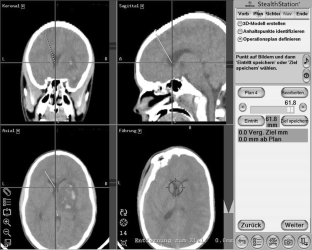

In cases of persistent elevated ICP despite maximal brain pressure management, the use of an intraventricular monitoring device with the possibility of cerebrospinal fluid drainage is favourable. We present the method of intracranial catheter placement by means of an electromagnetic navigation technique.